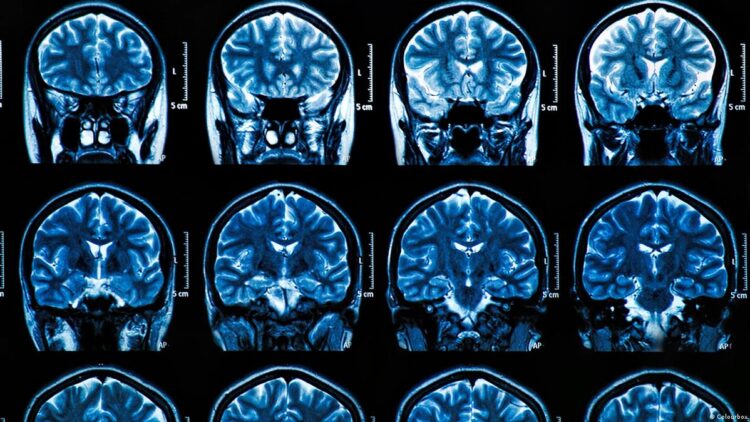

Os cientistas utilizaram “um conjunto de técnicas avançadas de imagem funcional e cerebral”, concretamente um “PET duplo”, uma tomografia “que mede, no mesmo doente, neuroinflamação e deposição de amiloide” e a ressonância magnética funcional “para medir a atividade cerebral em tarefas de memória”.